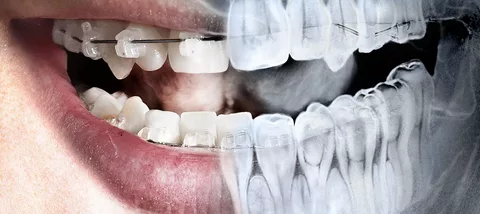

Панорамный снимок зубов используется специалистами в различных направлениях деятельности – стоматологии и ортодонтии. Ортопантомограмма делается в следующих случаях: Оценка состояния челюстей и тканей для обнаружения кист, опухолей, гранулем. Снимок делается при диагностировании пародонтита, позволяет назначить правильное лечение и отслеживать результат.